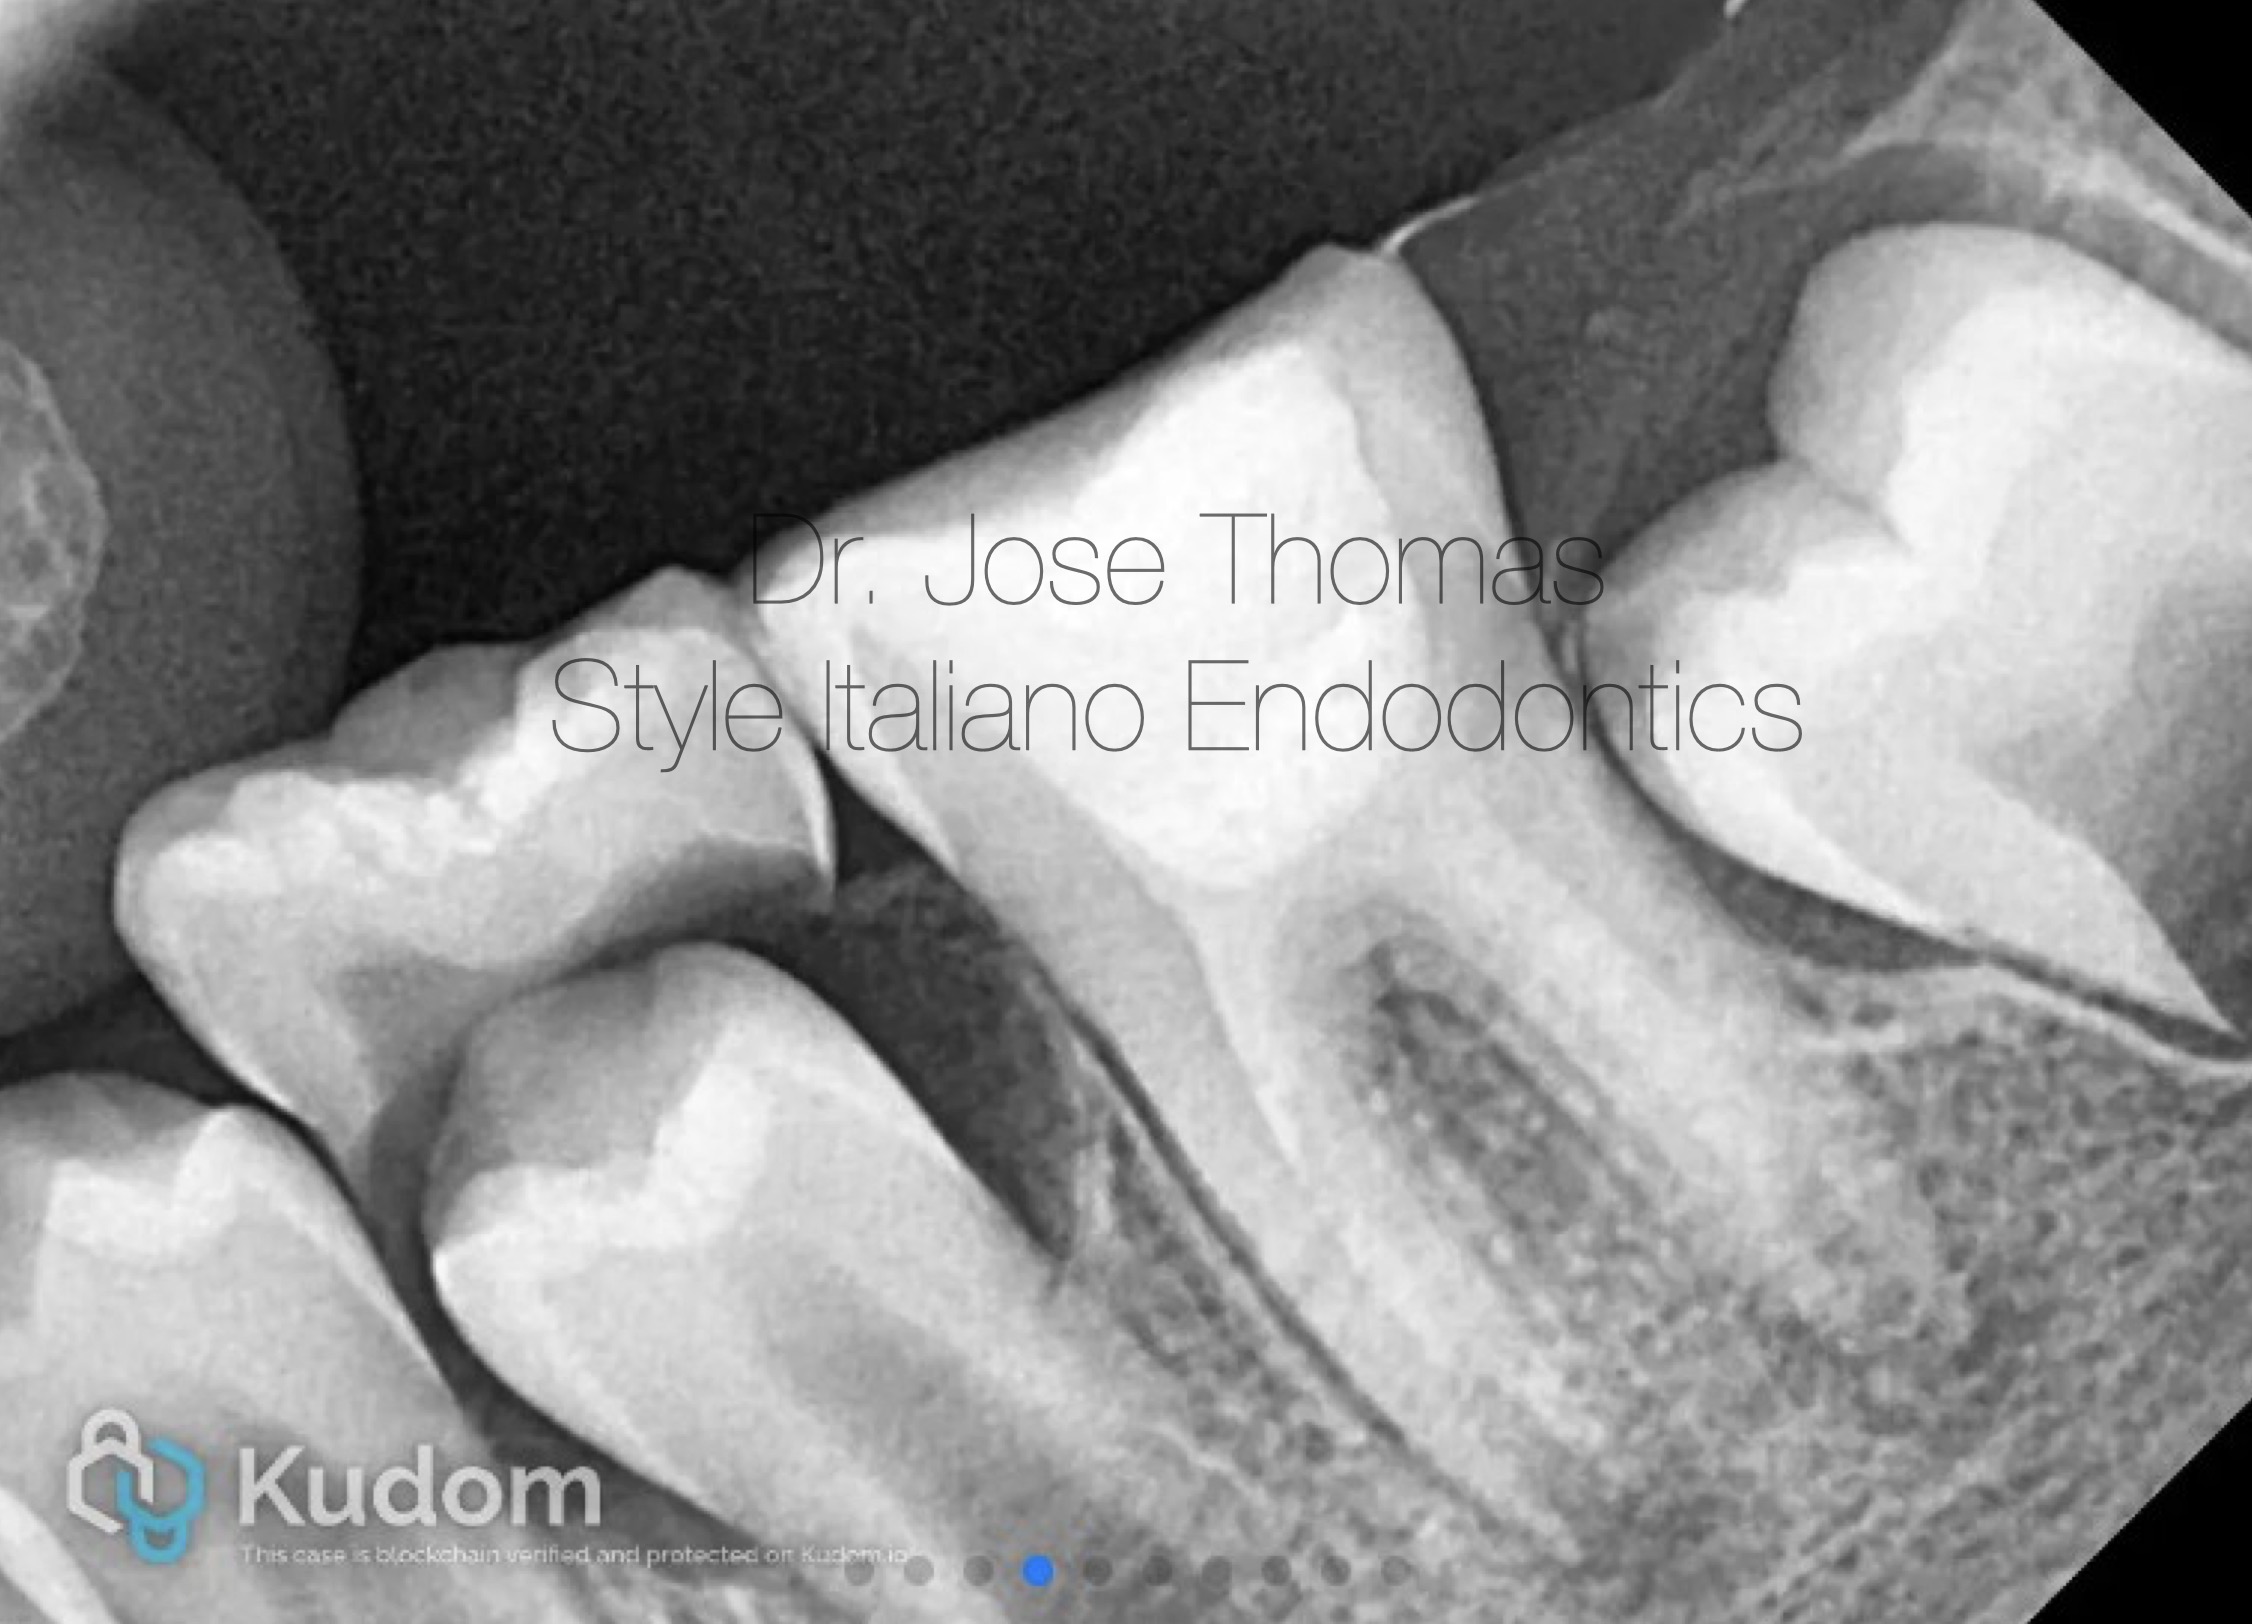

Fig. 1

Xray Shows deep carious lesion in tooth 36. The root length is nearly complete with wide open apical foramina and indistinct apical lamina dura around both mesial and distal roots.